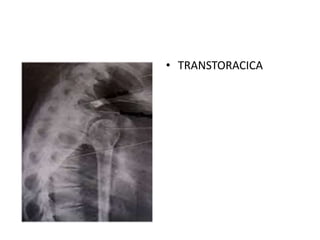

ESTUDIOS DIAGNOSTICOS

• AP DE HOMBRO

VERDADERA

• TRANSTORACICA

• PERFIL ESCAPULAR

• TAC

• RESONANCIA

MAGNETICA

ESTUDIOS DIAGNOSTICOS • APDE HOMBRO VERDADERA